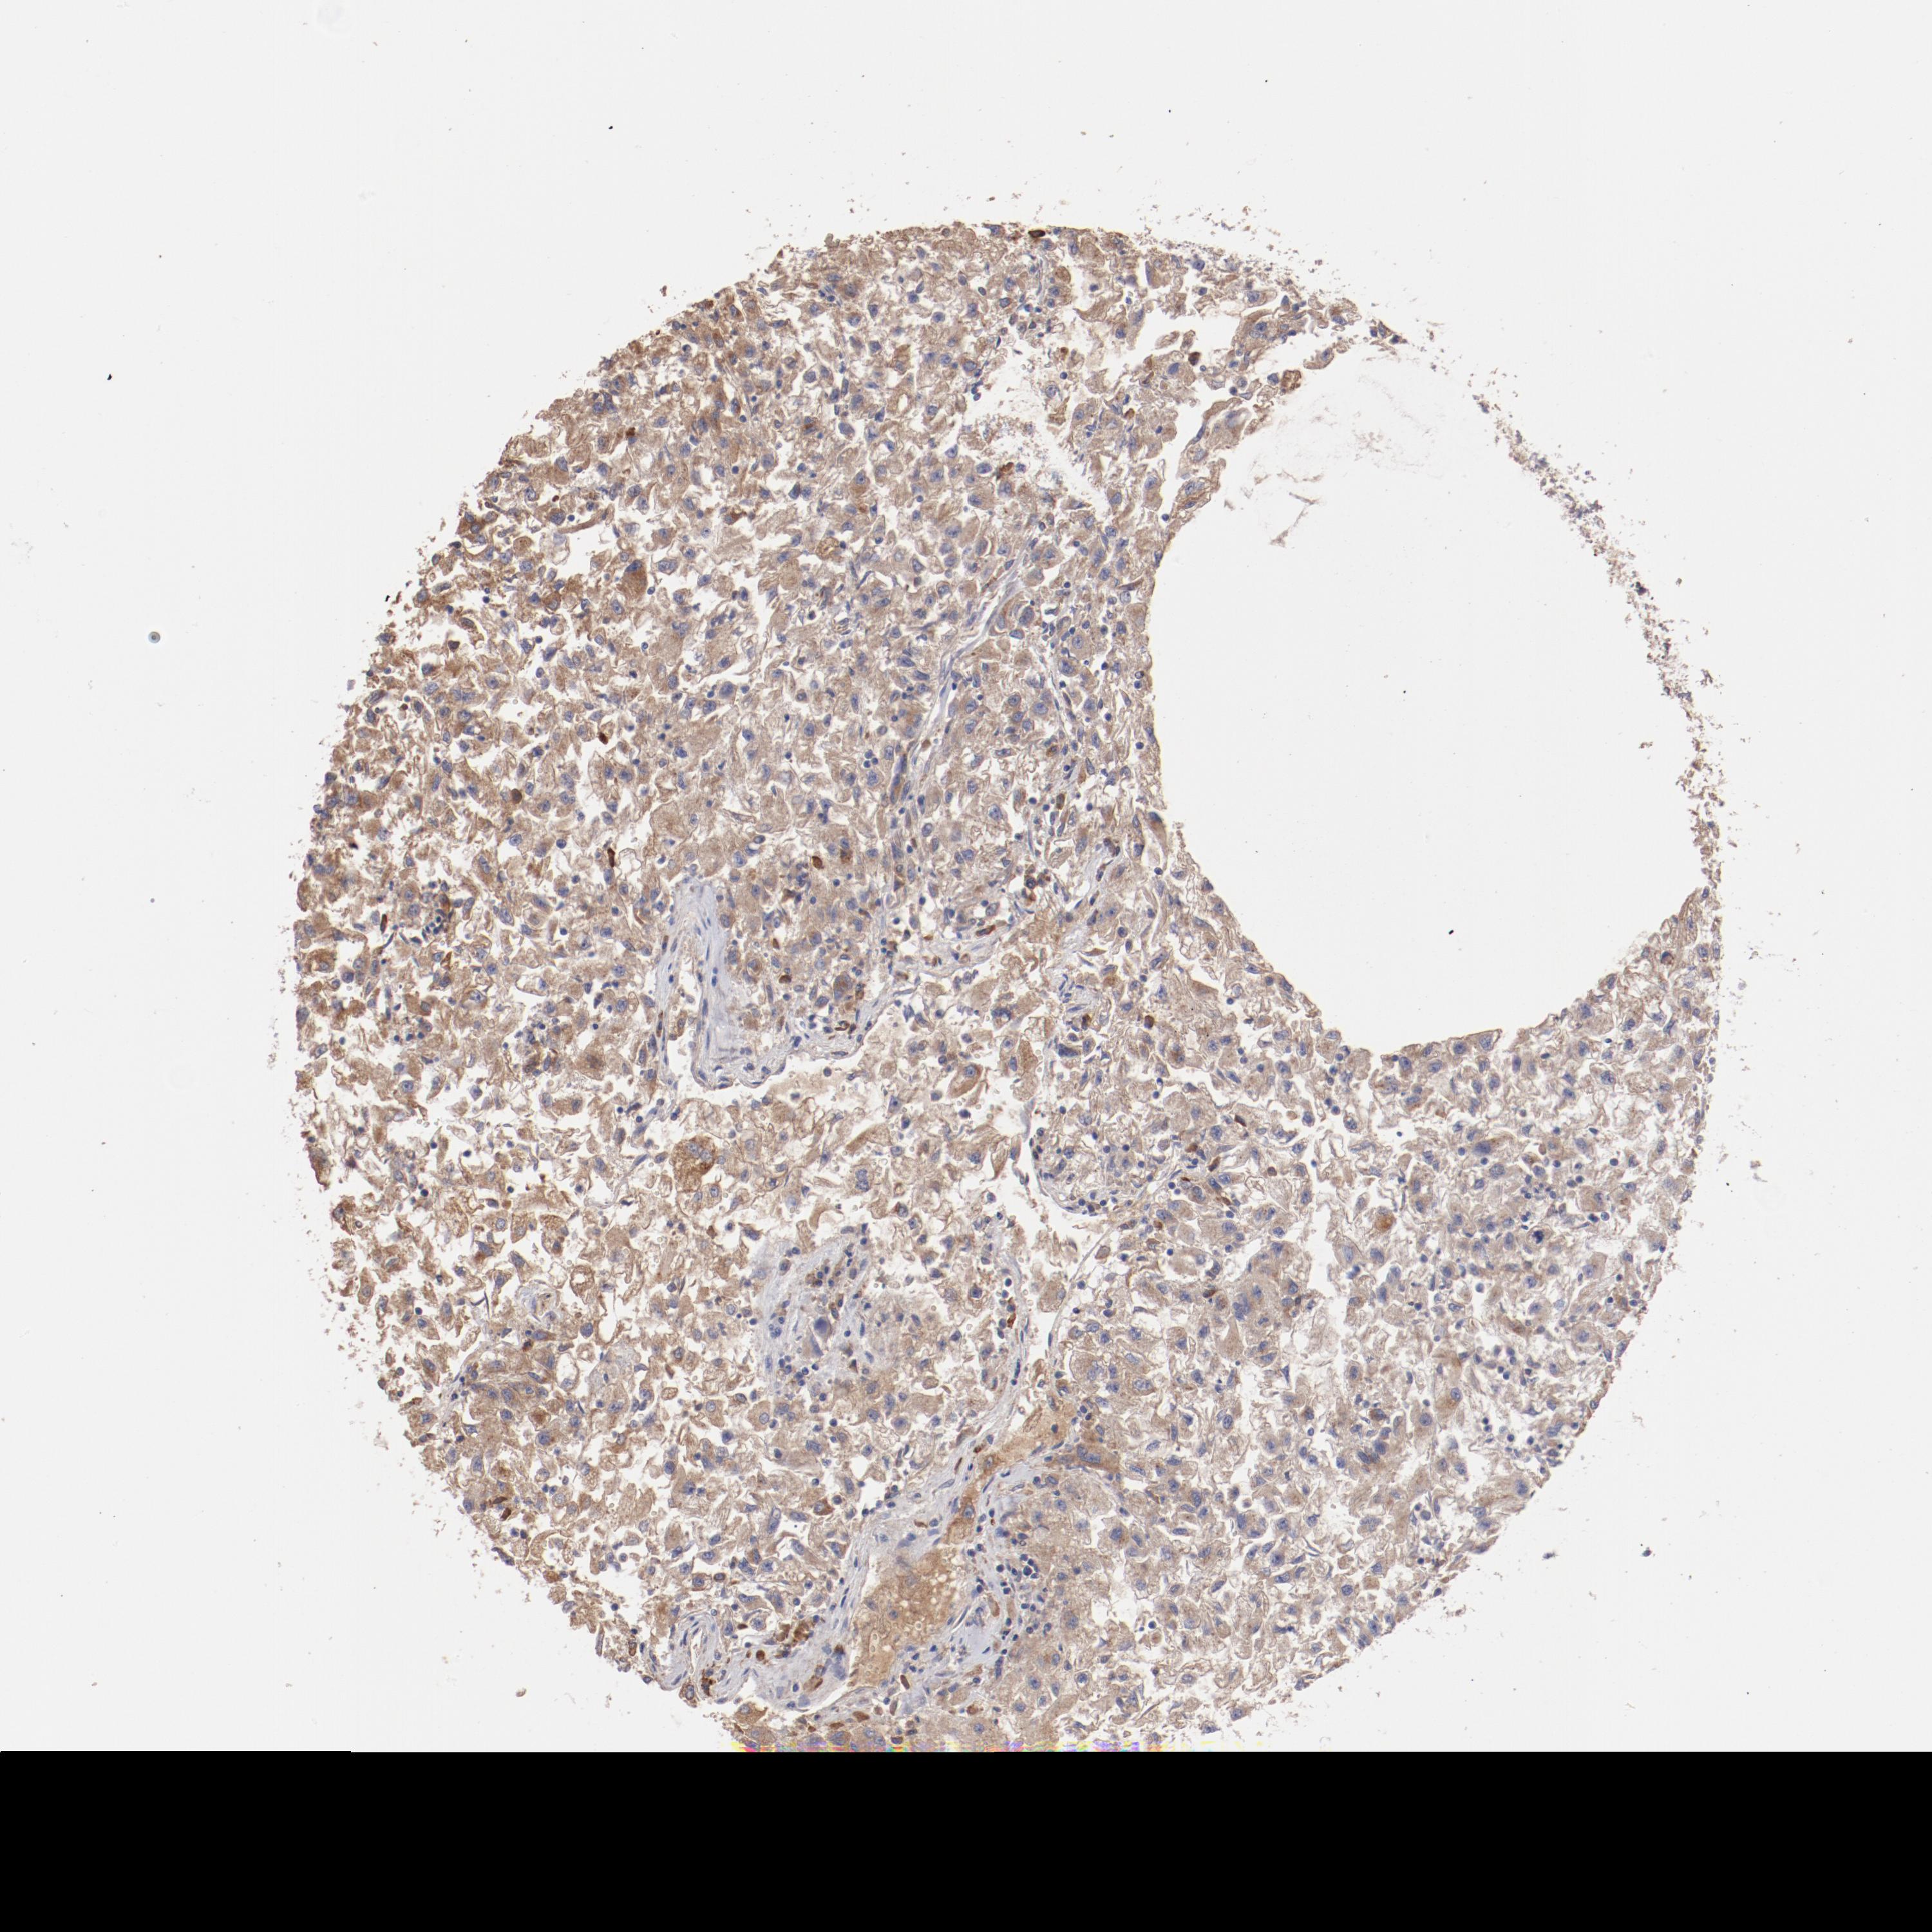

KIDNEY RENAL CLEAR CELL CARCINOMA (VALIDATION) - Interactive survival scatter ploti

The Survival Scatter plot shows the clinical status (i.e. dead or alive) for all individuals in the patient cohort, based on the same data that underlies the corresponding Kaplan-Meier plots. Patients that are alive at last time for follow-up are shown in blue and patients who have died during the study are shown in red.

The x-axis shows the expression levels (FPKM) of the investigated gene in the tumor tissue at the time of diagnosis. The y-axis shows the follow-up time after diagnosis (years). Both axes are complimented with kernel density curves demonstrating the data density over the axes. The top density plot shows the expression levels (FPKM) distribution among dead (red) and alive patients (blue). The right density plot shows the data density of the survived years of dead patients with high and low expression levels respectively, stratified using the cutoff indicated by the vertical dashed line through the Survival Scatter plot. This cutoff is automatically defined based on the FPKM cutoff that minimizes the p-score. The cutoff can be changed by dragging the vertical line or by entering a cutoff value in the square labeled "Current cut-off".

Under the Survival Scatter plot the p-score landscape (black curve; left axis) is shown together with dead median separation (red curve; right axis). Dead median separation is the difference in median mRNA expression between patients who have died with high and low expression, respectively. It is calculated as follows: median FPKM expression of dead patients with high expression - median FPKM expression of dead patients with low expression. This is intended to aid the user in visually exploring custom cutoffs and the associated p-scores and dead median separation.

Individual patient data is displayed and can be filtered by clicking on one or more of the category buttons on the top of the page. Categories describing expression level and patient information include: high, low, alive, dead, female, male and tumor stages. The scale of the x-axis can be toggled between linear and log-scale by clicking on the "x log" button. Mouse-over function shows TCGA ID, patient information and mRNA expression (FPKM) for each patient.

& Survival analysisi

Kaplan-Meier plots summarize results from analysis of correlation between mRNA expression level and patient survival. Patients were divided based on level of expression into one of the two groups "low" (under cut off) or "high" (over cut off). X-axis shows time for survival (years) and y-axis shows the probability of survival, where 1.0 corresponds to 100 percent.

NFKBIE is not prognostic in Kidney Renal Clear Cell Carcinoma (validation)

Best expression cut offi

Based on the FPKM value of each gene, patients were classified into two groups and association between prognosis (survival) and gene expression (FPKM) was examined. The best expression cut-off refers the FPKM value that yields maximal difference with regard to survival between the two groups at the lowest log-rank P-value. Best expression cut-off was selected based on survival analysis .

When clicking on this number, the vertical dashed line indicating cut-off, the interactive survival plot, and the Kaplan-Meier curve will be adjusted to show results based on the best expression cut-off.

: 18.93

P scorei

Log-rank P value for Kaplan-Meier plot showing results from analysis of correlation between mRNA expression level and patient survival.

N/A

TCGA RNA samplesi

RNA-seq data is reported as average FPKM (number Fragments Per Kilobase of exon per Million reads), generated by the The Cancer Genome Atlas (TCGA) .

Normal distribution across the dataset is visualized with box plots, shown as median and 25th and 75th percentiles. Points are displayed as outliers if they are above or below 1.5 times the interquartile range. FPKM values of the individual samples are presented next to the box plot.

Average pTPM 31.4

Number of samples 100